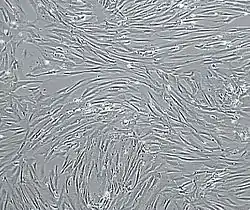

Vascular smooth muscle cells, isolated from human aorta, growing and forming a monolayer in cell culture.